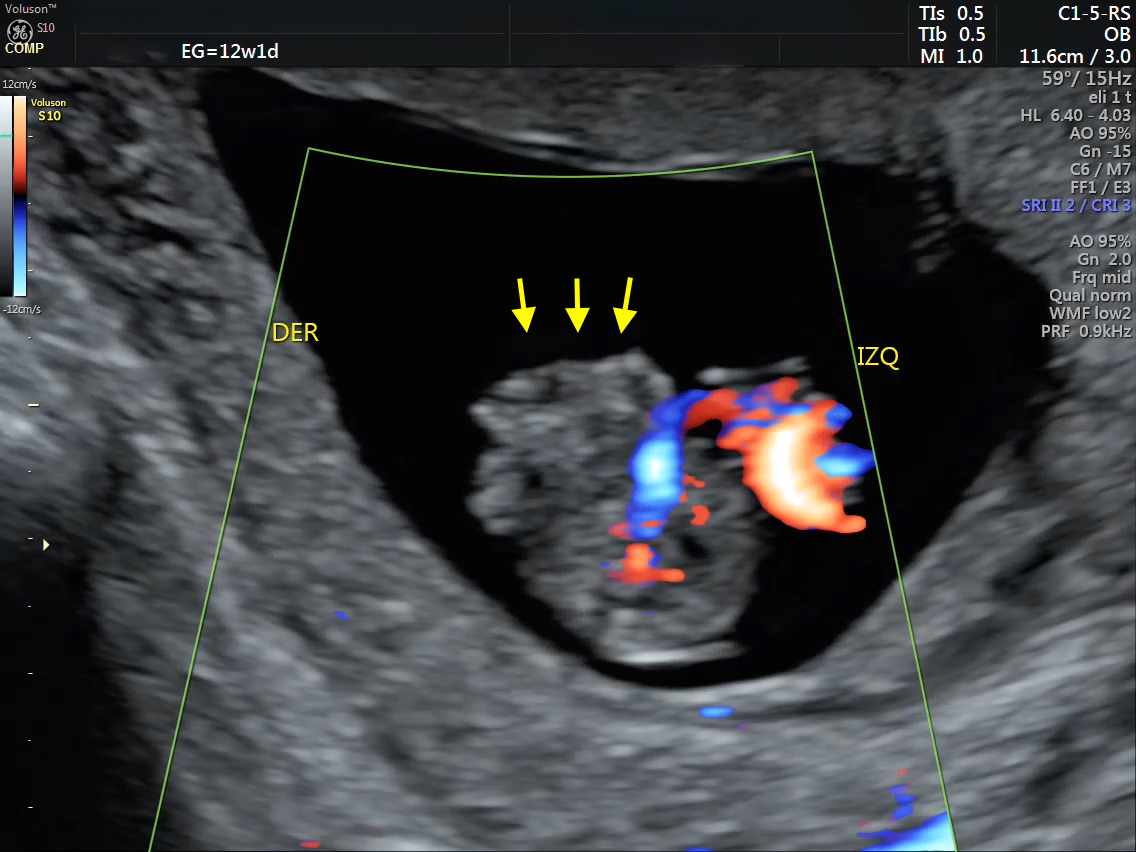

Se presenta el caso de una paciente de 23 años de edad, secundigesta, sin antecedentes personales ni familiares de relevancia. La paciente adjunta el estudio de screening de aneuploidías de la semana 11-14, que arroja bajo riesgo. Las imágenes 1 y 2 describen los hallazgos identificados durante la evaluación de la anatomía fetal en la semana 12. Las imágenes 3, 4 y 5 corresponden a los controles ecográficos posteriores, del segundo y tercer trimestre. La imagen 6 muestra al recién nacido. Seleccione la opción correcta: A. Corresponde a una hernia umbilical fisiológica con resolución más tardía. B. Corresponde a una gastrosquisis con cierre espontáneo intraútero. C. Corresponde a un onfalocele con ruptura del mismo. D. El defecto de pared cerró espontáneamente mejorando el pronóstico y riesgo de complicaciones gastrointestinales. Figura 1: se visualiza corte axial del abdomen fetal, a nivel de la inserción del cordón umbilical, con Doppler color en semana 12. Figura 2: se observa corte axial, a nivel de la inserción del cordón umbilical en la pared abdominal anterior, en semana 12. Figura 3: corte sagital a nivel de la inserción del cordón en la pared abdominal anterior, con Doppler color, en semana 20. Figura 4: corte axial del abdomen fetal, en semana 32, donde se identifica dilatación de las asas intestinales. Figura 5: corte axial del abdomen fetal, en semana 32, donde se identifica dilatación de las asas intestinales, con la utilización del Doppler color. Figura 6: se observa al recién nacido.

El caso presentado corresponde a una paciente de 23 años, secundigesta, sin antecedentes personales de relevancia, con embarazo único y espontáneo, que concurre al consultorio de ecografía para realizar un screening combinado del primer trimestre en la semana 12. Se evidencia solución de continuidad en la pared abdominal anterior, adyacente al cordón umbilical, con exteriorización de asas intestinales, compatible con gastrosquisis (Figuras 1 y 2).

A las 23 semanas de gestación, se realiza una evaluación anatómica completa donde no se pudo constatar la exteriorización de asas intestinales descrita en estudios previos. A nivel intra-abdominal, se evidenció en la región adyacente a la inserción del cordón, asas intestinales dilatadas, con pared ecogénica y engrosada, la mayor de 8,5 mm. Estos hallazgos fueron interpretados como intestino evanescente en contexto de gastrosquisis (Figura 3). El resto de la anatomía fetal impresionó conservada, con evaluación ecocardiográfica fetal normal en semana 25.